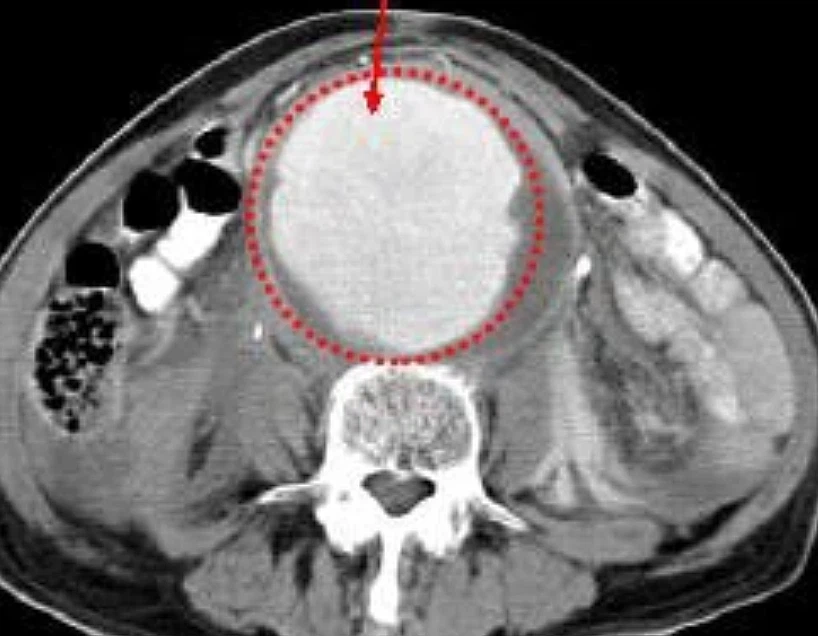

복부전산화단층촬영(Computed Tomography)

복부대동맥류의 조영에 가장 정확한 검사이며 동맥류의 크기나 범위, 다른 혈관과의 관계를 명확히 보여줍니다. 팔에 있는 정맥에 소량의 조영제를 주사한 후 CT로 동맥만 잘 보여주는 촬영방법입니다.

<복부전산화단층촬영 검사로 확인한 복부대동맥류사진>